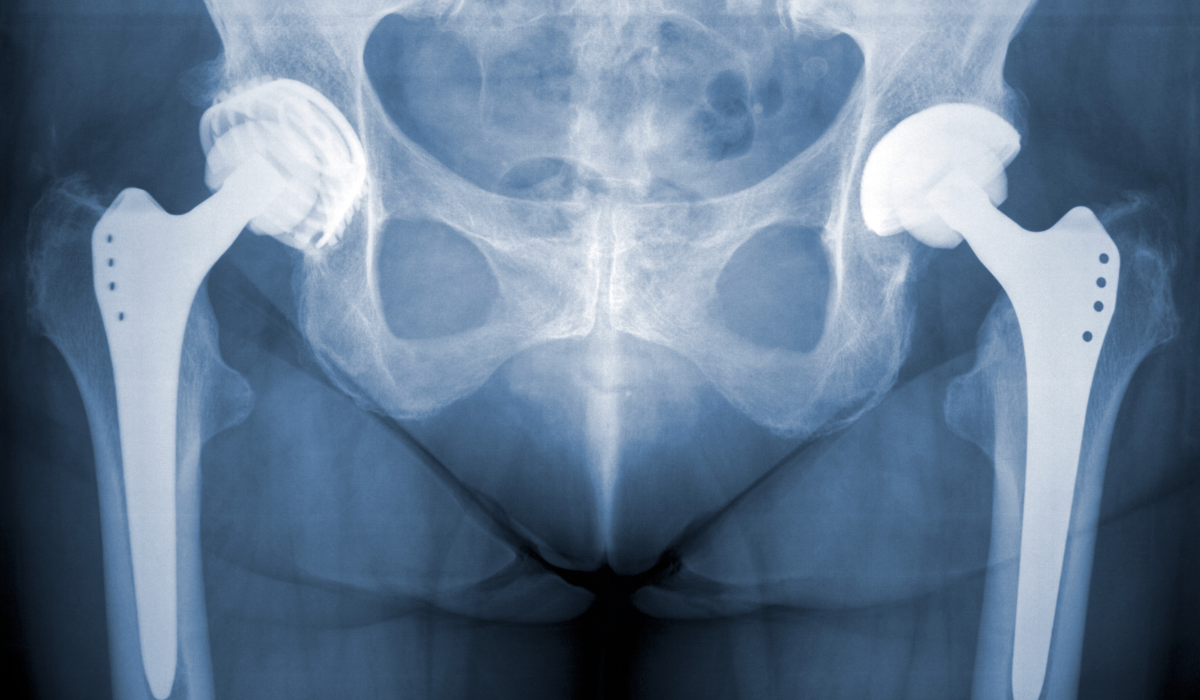

In this surgery, the damaged ball-and-socket joint is replaced with a prosthetic implant, typically made of metal, ceramic, or high-grade plastic. The artificial joint mimics natural motion, allowing for pain-free walking, climbing, and daily tasks. Advances in surgical techniques—especially minimally invasive and muscle-sparing approaches—have improved recovery times, reduced scarring, and minimized blood loss. Most patients can walk with assistance within a day after surgery and begin structured physiotherapy soon after.

During surgery, our surgeons use modern minimally invasive or posterior approaches to replace the hip joint with precision. The procedure is performed under spinal or general anesthesia in a sterile environment. We utilize biocompatible implants that match the patient’s anatomy, ensuring stability, comfort, and longevity. Special care is taken to minimize tissue trauma and reduce the risk of complications.